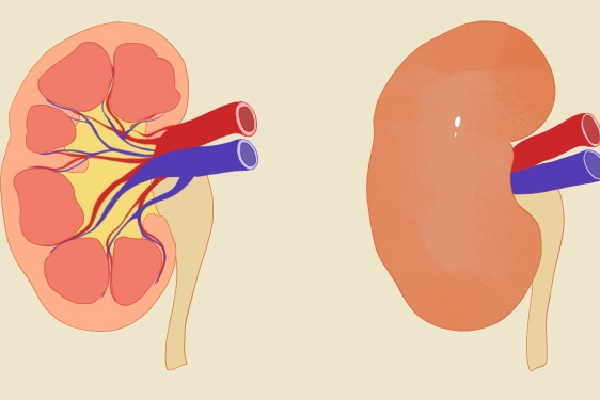

生活中,不少人常感到乏力、精神不济,尝试多种方法后仍无改善,进而关注到补肾,想知道:补肾可以提高精力吗?肾藏精、主元气,肾精充足与否直接影响身体元气盛衰,合理补肾对提高精力有积极作用。

通常可以提高精力。在中医理论中,“肾为先天之本”,不仅掌管生殖与泌尿系统,还主导人体的生长、发育和能量储备。我们常说的“精气神”,其中的“精”就源于肾。当肾气充足时,人会感觉精力充沛、体力好、注意力集中;而肾虚则常表现为疲劳、腰膝酸软、记忆力减退、性功能下降等。

因此,科学地补肾,实际上是帮助身体恢复能量平衡,自然就能提升整体精力水平。